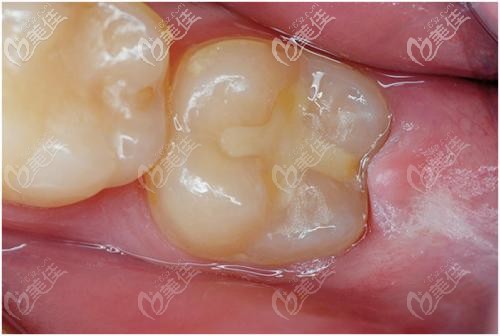

輕微齲齒補牙選擇美國3m和日本松風哪個好? b10935 G0 V0

牙齒蛀了個洞是否需要補牙要看情況,淺齲和中齲 “補牙”即可,深齲才需要做根管治療,那么輕微齲齒補牙選擇哪種材料好呢?

四歲牙齒蛀牙有洞補牙選擇樹脂、玻璃離子、陶瓷嵌體哪種材料? b1850 G0 V0

三四歲的小孩子稍不注意就會長蛀牙,看著那一個個的牙洞,家長很是著急,其實如果蛀牙夜里不疼的話,及時做補牙還是可以的。